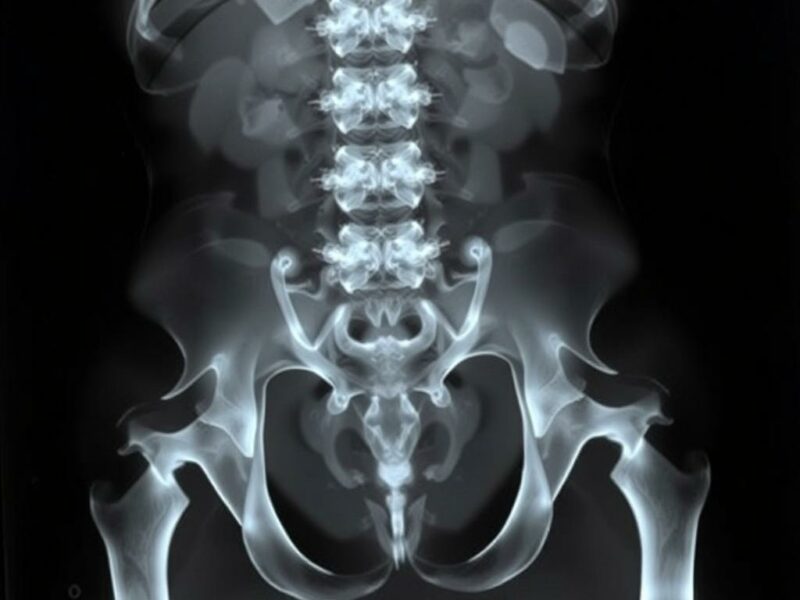

La radiografía simple de abdomen —conocida en muchas consultas como abdomen plano, abdomen sin preparación o abdomen de urgencias— evoca imágenes familiares: la placa en decúbito supino, la imagen vertical en bipedestación, la búsqueda de niveles hidroaéreos, o la detección de aire libre subdiafragmático. Para muchos profesionales de la salud sigue siendo la prueba más accesible, rápida y económica frente a un paciente con dolor abdominal o distensión. Sin embargo, la pregunta que late en la práctica cotidiana es: ¿qué puede realmente aportar esta técnica simple y cuáles son sus límites? En este artículo amplio, conversacional y orientado a la práctica clínica reflexionaremos sobre las principales limitaciones de la radiografía estándar del abdomen, explicando de forma clara por qué en numerosos escenarios ha cedido terreno ante la tomografía computarizada (TC) y la ecografía, y cuándo sigue siendo útil. Además, veremos qué signos radiológicos son fiables, cuáles son ambiguos, qué factores técnicos y del paciente condicionan la interpretación, y cómo integrar la radiografía simple en un algoritmo diagnóstico razonable y seguro.

La radiografía abdominal tiene sus orígenes en los albores de la radiología diagnóstica y, durante décadas, fue la principal herramienta para evaluar complicaciones quirúrgicas, obstrucción intestinal y presencia de masas calcificadas. Su fuerza residía en la disponibilidad: casi cualquier centro de salud tenía la posibilidad de obtener una placa en minutos. Con la llegada de la TC y la ecografía de alta resolución, el papel de la radiografía simple cambió. Hoy, la radiografía abdominal sigue siendo la primera línea en muchas áreas de urgencias y centros rurales, útil para evaluar neumoperitoneo (en algunos casos), obstrucción con numerosos niveles hidroaéreos y cuerpos extraños radiopacos. Pero su capacidad de visualizar órganos sólidos, lesiones inflamatorias tempranas o procesos retroperitoneales es limitada. Conocer ese territorio de sombras y certezas es vital para no sobreinterpretar ni subestimar hallazgos.

- Radiografía simple: útil como cribado inicial en obstrucción intestinal, para localizar cuerpos extraños radiopacos, valorar la presencia de gas libre en posiciones adecuadas y en entornos con recursos limitados.